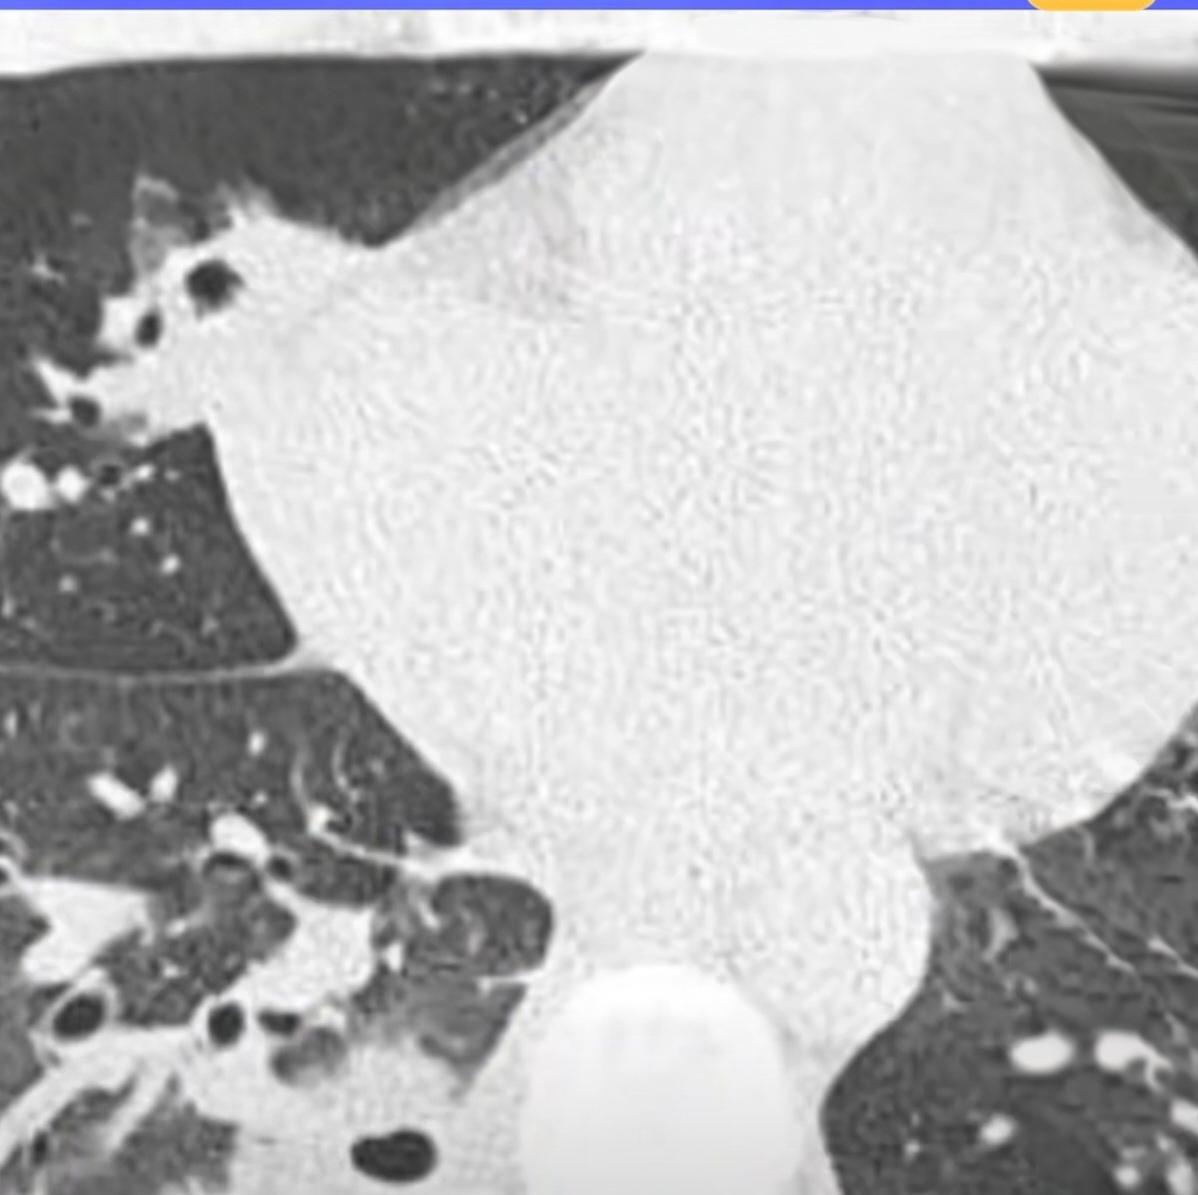

挤一颗痘痘竟致肺里现十几个空洞!大二学生的惨痛教训 20岁的大二学生小林为备考熬夜后,脸部冒出一颗黄豆大小的红肿痘痘。因觉得影响美观,他未洗手便对着镜子将其挤掉,当时看着脓水流出还倍感清爽。 然而几天后,痘痘不仅持续化脓,小林还出现发烧、咳嗽、咳痰等症状,退烧药仅能暂时缓解不适,右下胸更是传来针刺般的疼痛,深呼吸、咳嗽时疼得直冒冷汗。熬至第三天,体温升至39℃的小林紧急前往宁波大学附属第一医院就诊。 接诊的丁群力主任医师通过CT检查发现,小林肺内出现十几个空洞,部分肺组织已坏死,确诊为血源性肺脓肿。细菌培养和基因检测显示,其血液中检出的金黄色葡萄球菌是“元凶”——该细菌原本存在于皮肤表面,而小林挤的痘痘位于脸部“危险三角区”,未洗手的操作让细菌在挤压压力下进入血管引发败血症,进而随血流侵入肺部,侵蚀肺组织导致严重感染。医生提醒,脸部危险三角区的痘痘切勿随意挤压,皮肤出现感染需及时科学处理,避免引发致命风险。